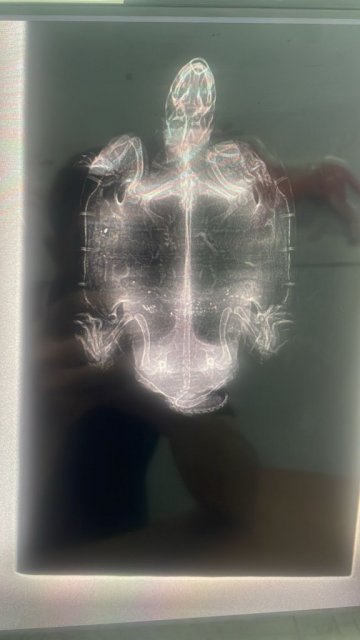

Добрый день! Наш самец 15 лет (20 см карапакс), 900 гр, наелся герметика с мелкими камешками, которым покрыт островок. В пн поел как обычно, во вторник тоже, а в среду после кормешки срыгнул всю еду. С едой вышли два куска герметика размером с пятак. В четверг срыгнул остатки еды и еще два длинных куска герметика. От еды оказывался в чт. В пт съел кусочек рептомина. В пт после обеда отвезли в ветклинику. Сделали рентген. Врач сказала, что нет закупорки. Сегодня вс третий день носим в клинику на уколы (комплекс витаминов и антибиотик). Сделали клизму. Все вышло. Врач уверяет, что нет закупорки. Вялый. Поел 6 кубиков мотыля. Но сам не просит еду как обычно. Пока не видели помёт. В среду, после того как стошнило, он испражнился большой зеленой плотной какулей размером с палец большой. Это рептомин с прошлой пятницы видимо вышел. Больше помет не видел. Но он и не ел толком. Немного мотыля с субботы. Жду помет. Попросил сделать контрастный снимок. Врач отговорил, сказала барий опасен для черепахи, может умереть. Что делать? Помогите пожалуйста. Очень люблю этого зверька. Он офисный, корпоративный. 15 лет ему уже.